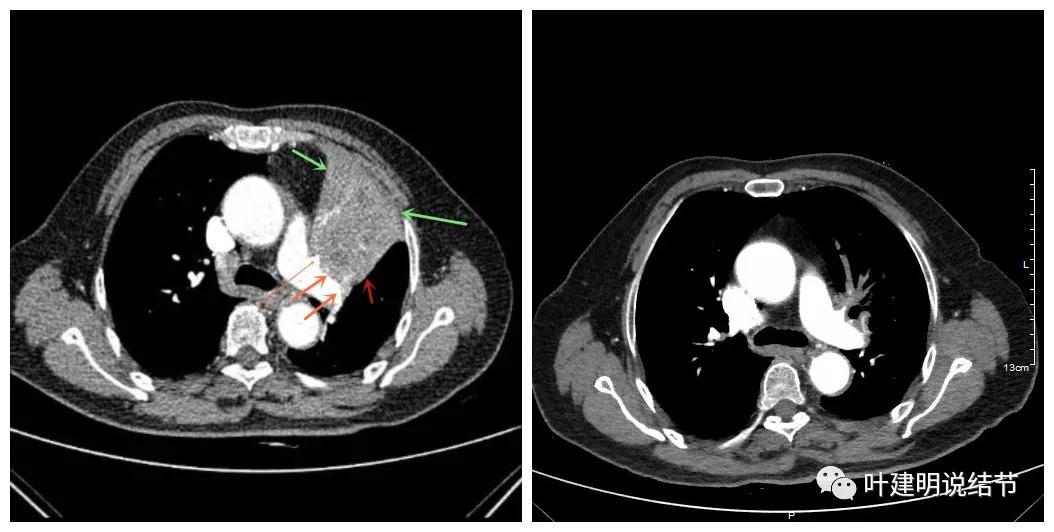

可见效果相当的好,如果我们把差不多同样层面的放到一起对比,更能显示化疗加免疫的惊人效果:

我样的治疗效果,显然超出了我们之前的预期,那么接下来拟选择行手术治疗,初定左上叶袖式肺叶切除加淋巴结清扫,但因为肺门区仍有软组织影,与肺动脉的关系仍密切,肿瘤与肺动脉间能否游离开来还是未知数,但至少得努力争取,鉴于患者年纪虽大,肺功能指标尚可,血气分析也基本正常,所以与患方沟通后确定行手术探查,但也也说明有万一全肺切除的可能(虽然这种可能性较小)。